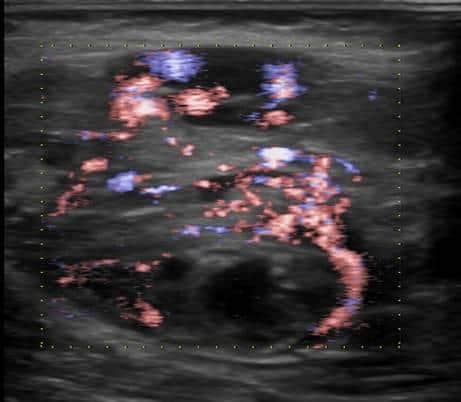

U xơ cơ

» Thông tin: Nữ giới – 3 tháng tuổi.

» Lâm sàng: Sưng vùng đùi.